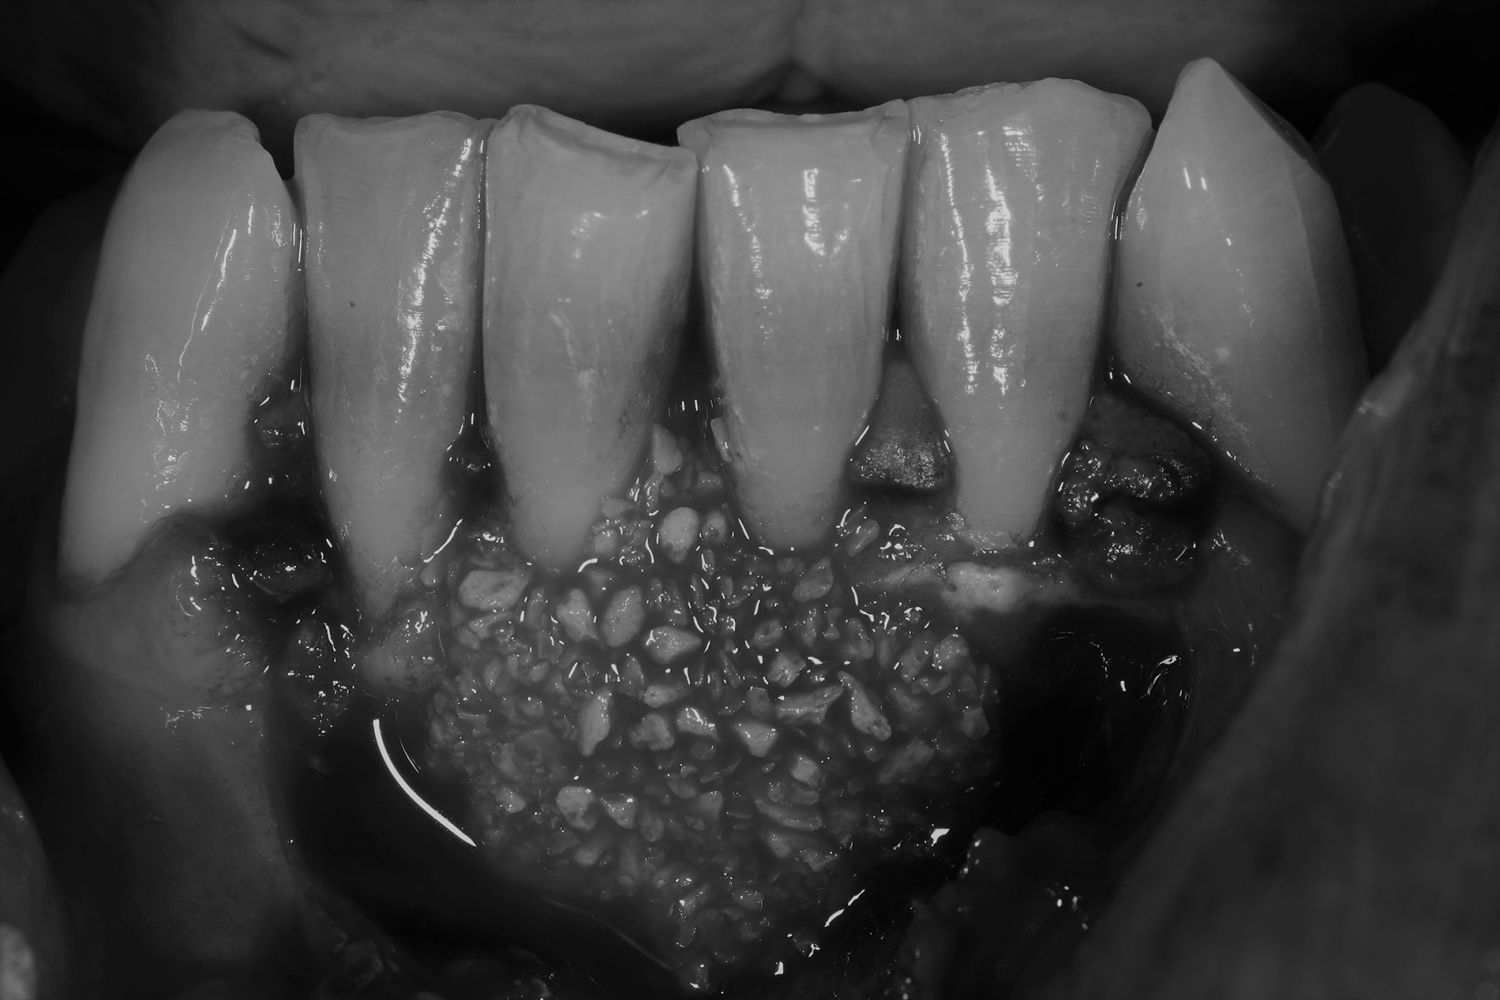

Caso de cirugía periodontal

Cirugía periodontal en un paciente